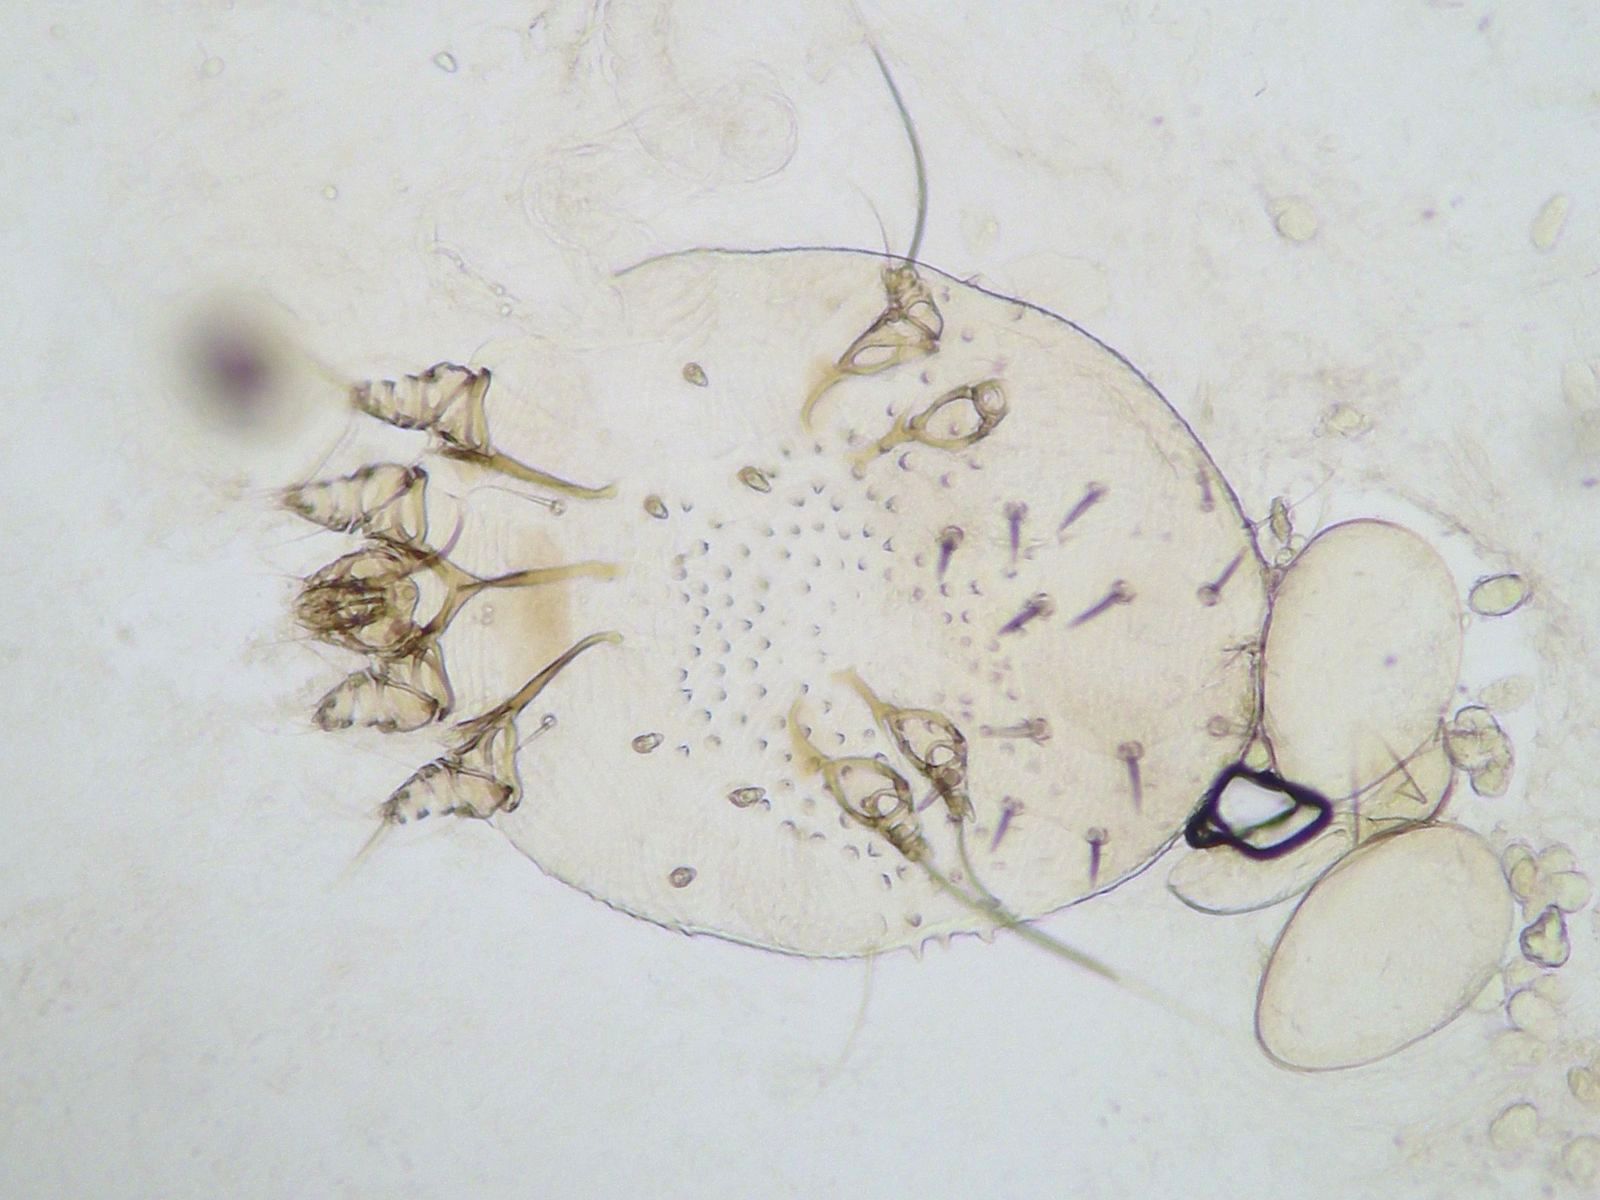

Scabies can be definitively proven by visualizing the scabies mite under a microscope in a skin scraping. For this, a small piece of the stratum corneum is scraped or cut off with a knife from the most suspicious areas. This scrap of skin is then soaked for fifteen minutes in a KOH (potassium hydroxide) solution. This causes the cells to fade, making any mites or eggs clearly visible under a microscope. Another method is to examine the skin very closely with a dermatoscope (a lighted magnifying glass) and a drop of oil underneath. With this dermatoscopy, larger mites can sometimes be seen easily.

![Scabies mite in the KOH preparation, artistically photographed by Dr. LLA Lecluse (click on photo to enlarge) [source: www.huidziekten.nl] Scabies mites in the KOH preparation](../../images/schurftmijtKOH1z.jpg) |

![Scabies mites in the KOH preparation (click on photo to enlarge) [source: www.huidziekten.nl] Scabies mites in the KOH preparation](../../images/schurftmijtKOH2z.jpg) |

![Scabies mites in the KOH preparation (click on photo to enlarge) [source: www.huidziekten.nl] Scabies mites in the KOH preparation](../../images/schurftmijtKOH3z.jpg) |

| adult scabies mite |

adult scabies mite |

egg-laying female |